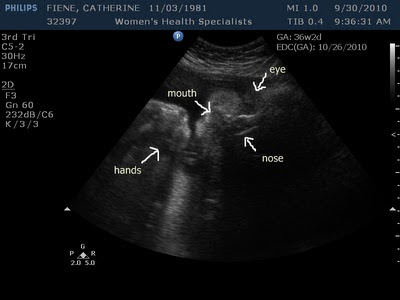

I can't seem to get away with having a small baby. John was born about 2 1/2 weeks early at 8 lbs 5 oz and Gus came into the world a week early weighing in at a whopping 9 lbs 12 oz. I had high hopes for this baby as I haven't gained that much weight and up until about 3 weeks ago I was measuring right on track. Seriously, I was ecstatic about the possibility of holding a little bundle of joy. However, it just isn't meant to be. I had a sonogram today to determine the baby's size since I've been measuring about 4 weeks ahead and my "little" bundle of joy is already 8 lbs 7 oz. I know sonograms can be off, but the wonderful sonogram tech at my doctors office is hardly ever off and if she is it is only by a few ounces. Aside from the weight, his/her head is measuring at 40 weeks 2 days. I keep telling this baby that he/she can come anytime and to please not make me wait too much longer.